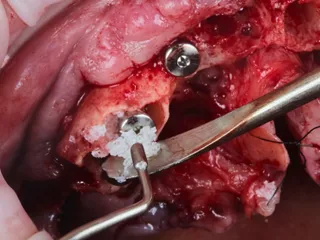

8. The existing gaps were filled with Straumann ® XenoGraft biomaterial to support the bone remodelling processes that occur post extraction.

8

15. The gaps between the implant surface and the internal wall of the socket were filled with Straumann® XenoGraft biomaterial.

15